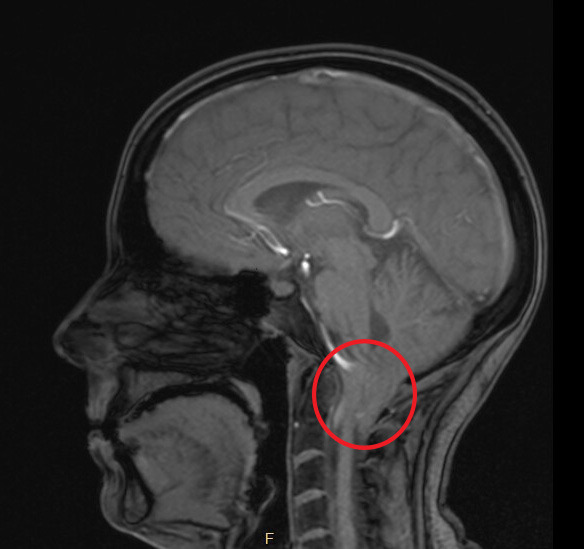

She has a condition called chiari malformation, which is a structural defect in the base of the skull and brain, wherein part of the cerebellum extends down into the spinal canal through the opening at the base of the skull. This is compressing her brainstem and spinal cord and will require surgery to remove a portion of her skull and upper neck vertebrae to relieve pressure in that area, as she has been experiencing worsening symptoms recently. Her father was a combat veteran who was exposed to Agent Orange in Vietnam, which may possibly have contributed to her development of this condition.